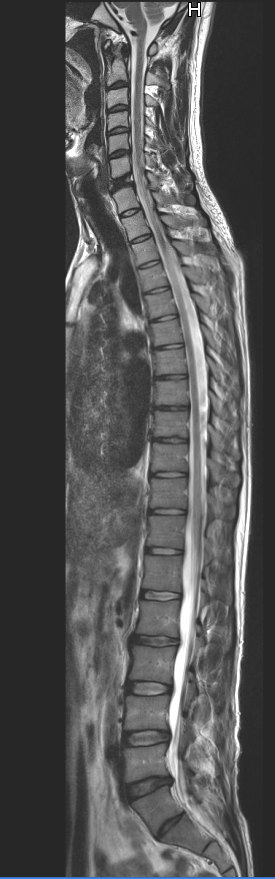

ȸ̵: sdworker ȸ̸: sdworker@naver.com , ü Ư Ű 176 Cm ü 63 Kg 35 ȯ 1C.ٿ, 6C.ڸ , 6C.ھ Ḳ , 6C.ڻ , 6T., 5L.ڹ߸̳ , 5L. , 5L.ڹ߹ٴ̳ ߵ ̳ ȭŸ̳ , ()κп ̻ ܵ. ,㸮ũ, Ͽ ũ(߰Ż), ũ(߰Ż)ġ, հ , , հ , ġ, , Ḳ , , Ḳ ġ Ʋ 㸮ũ(߰Ż) ߿ ġ , 㸮 ̳ ġ ٸ ġ Ƹ ġ ͳ ˻ õ ۳11 㸮 ߴµ 12 ʹ 㸮ٴ ʴٸ ܰ ũ ǽɵȴϿ 3 ġḦ Ͽ Ծϴ. ߺ mri ô45̿ ũ Ƣ Ű йϰ ִ ¿ ٸ ũ鵵 ణ Ƣ ִ ¿ϴ. **ѹ溴 3 ħ,ħ,,ġḦ 712Ͽٸ ô mri 㸮 ٽ Ϸ 帰 ó C7 йڰҰ Խϴ. 뺴 Ѱ ʰ Ȱó δٰ ϸ 1~2 ʿϴٰ Դϴ. ˱ Ѱ µ йڰ ִٴ ˰ ں Ű ʹ Ἥ ϰ ʾ ձ Դϴ. ´ Ը ּ. Źմϴ. 716 1030п Ƚϴ. |